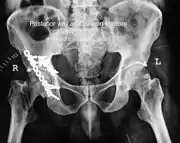

To understand the fracture pattern of a fractured acetabulum, it is essential to have minimum three x-ray views, though use of CT scan with 3-D reconstruction of images has made understanding of these fractures easier.

- Pelvis with both hips antero posterior view. This view shows six important landmarks of the acetabulum, specifically:

- Iliac oblique view. This view shows the whole of the ilium, the posterior column, and the anterior wall

- Obturator oblique view. Shows the anterior column and the posterior wall.